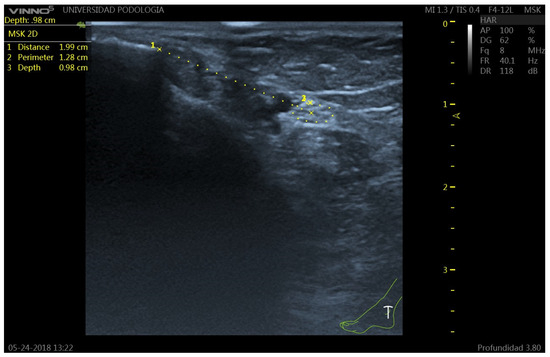

Background: Clinical procedures involving the tibial nerve (TN) are complex procedures due to its deep anatomical position and the variability of its course in the retromalleolar region. Few studies have described the ultrasound characteristics of the TN in vivo. This study aims to describe the ultrasound position of the TN and its relationship with the posterior tibial artery (PTA) at the retromalleolar level, evaluating the influence of sex, weight, height, and body mass index (BMI). Methods: A cross-sectional ultrasound study was performed on 100 volunteers. Anthropometric variables were recorded. Ultrasound measurements included the TN perimeter, distance from the medial malleolus to the TN center, depth, and spatial relationship with the PTA. Statistical analyses included Student’s t-test, ANOVA, Chi-square test, and Pearson’s correlation coefficient, with a significance level of p < 0.05. Results: The mean distance from the TN to the medial malleolus was 2.17 cm, and its mean depth was 0.91 cm. The most common anatomical pattern was Type I (TN posterior to the PTA) (60%). Sex influenced TN position, with men showing greater distances from the medial malleolus to the TN center (2.42 vs. 1.99 cm) and women showing greater depth from the skin surface to the upper edge of the tibial nerve perimeter (0.94 vs. 0.86 cm). Weight (p = 0.004), height (p < 0.001), and ankle circumference (p = 0.006) correlated significantly with TN location, whereas BMI did not (p = 0.253). Conclusion: These findings provide clinically relevant reference data that may improve the precision and safety of different tibial nerve procedures. Full article